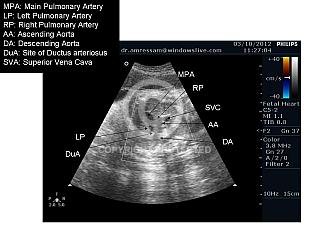

Fetal Chest and Heart (43)

Great Vessels View (15)